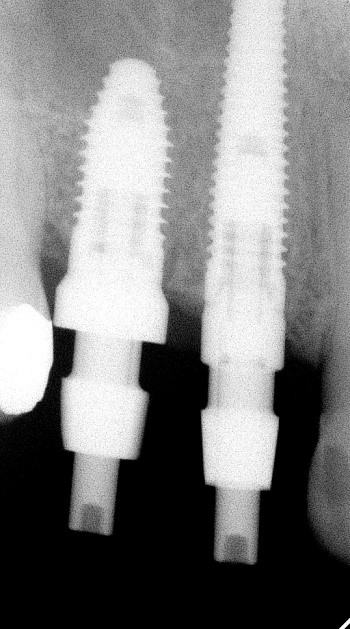

Современный дентальный имплантат — это небольшой титановый винт, прочно вставленный в кость, во внутреннюю полость которого вставлен абатмент, который уже выступает над костью и десной в полость рта. К абатменту крепится несъемная коронка, мостовидный протез или специальный вид съемного протеза — гибридный протез.

Пациентка обратилась с кариесом корня 14 зуба и 15 зуба с разрушением коронковой части зуба, ранее леченного с установкой анкерного штифта.

Имплантация 14, 15 зуба с циркониевой коронкой на импланте: